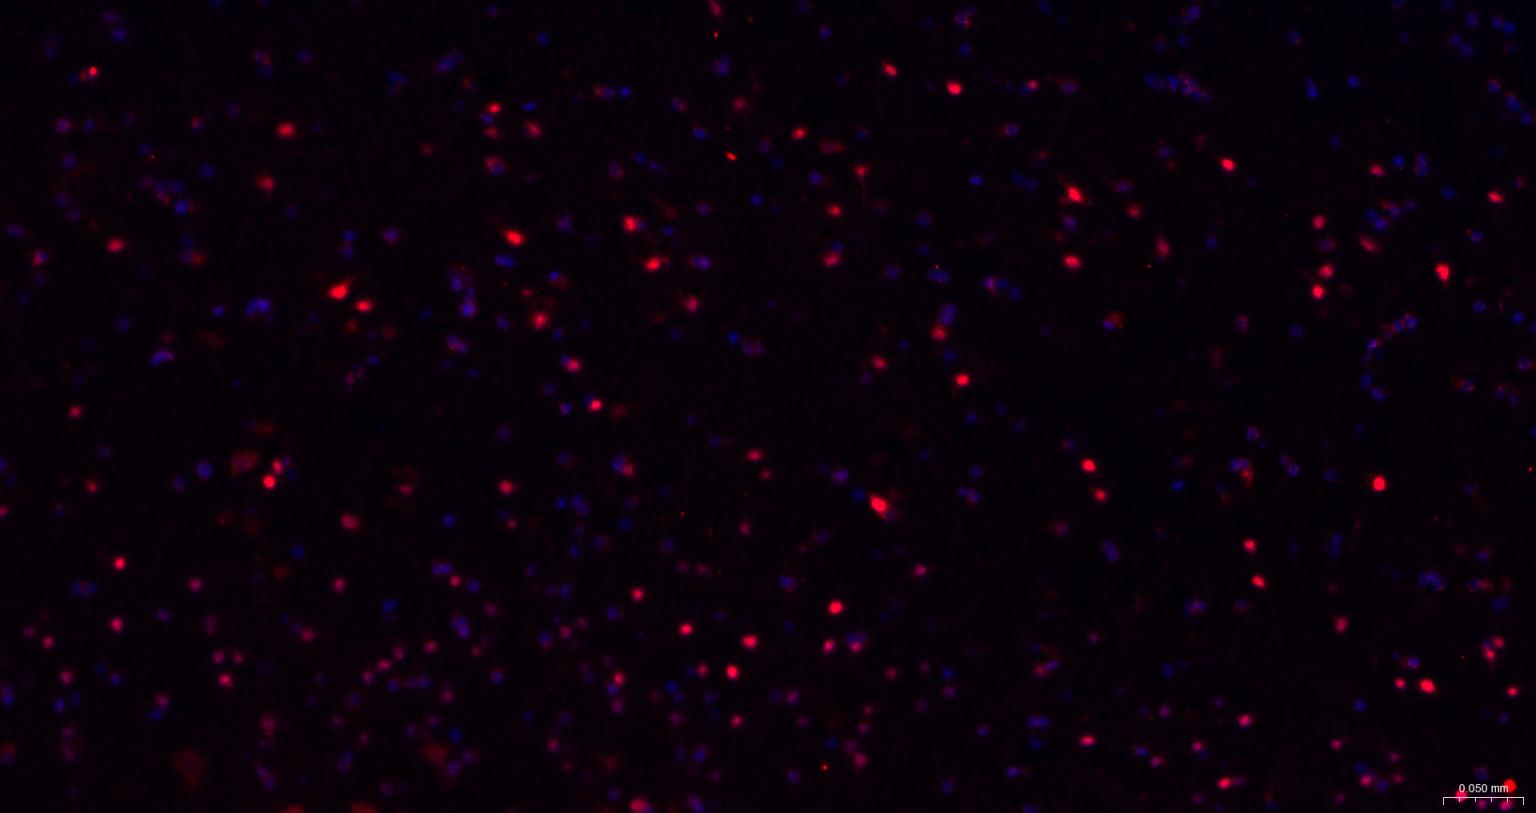

Paraformaldehyde-fixed, paraffin embedded Rat Cerebrum; Antigen retrieval by boiling in sodium citrate buffer (pH6.0) for 15 min; The section was incubated with TBR1 Monoclonal Antibody, Unconjugated (bsm-60877R) at 1:200 overnight at 4°C. Followed by conjugated Goat Anti-Rabbit IgG antibody (Red, bs-0295G-BF594), DAPI (blue, C02-04002) was used to stain the cell nuclei.